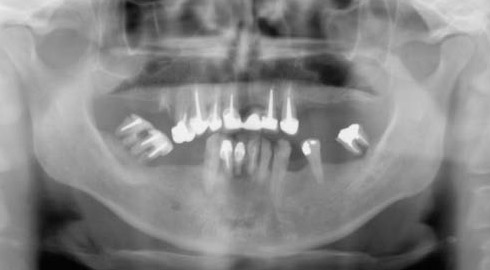

Le choix se fait en fonction de l’emplacement, de la quantité d’os disponible, et des éléments anatomiques environnants à partir d’examens cliniques, radiologiques et scanner de la zone à implanter.

Le chirurgien-dentiste après une anesthésie locale pratique une incision, puis il décolle la gencive pour accéder à l’os alvéolaire.

Ensuite il prépare l’emplacement de l’implant dans l’os en passant plusieurs forets de diamètre croissant. Le forage de l’os se fait à vitesse maîtrisée et lente sous irrigation, pour respecter la structure osseuse et éviter tout échauffement de celle-ci. Le praticien arrête lorsqu’il a obtenu un puits d’un diamètre très légèrement inférieur à l’implant à poser.

L’implant est placé dans l’os le plus souvent par vissage et doit avoir une liaison forte avec l’os. Le praticien replace alors la gencive et pose des points de suture.

Il faut attendre après la pose de l’implant, l’ostéo-intégration, qui peut durer plusieurs mois. L’implant va se souder complètement avec l’os et contrairement à la dent naturelle, il n’y a pas de souplesse ou de mobilité physiologique dues au ligament alvéolo-dentaire.